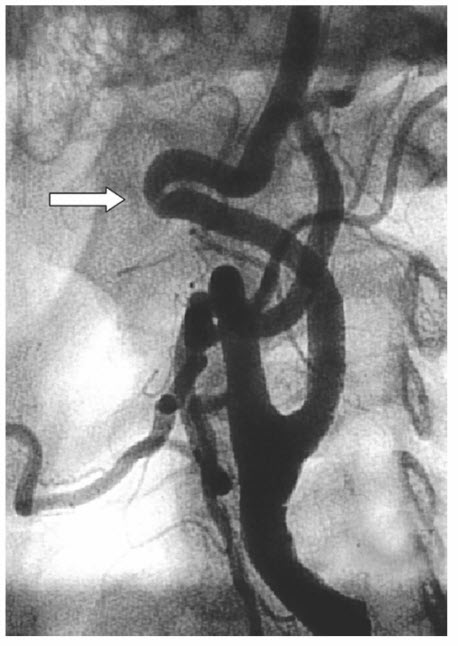

Fibromuscular dysplasia (FMD) usually involves mediumsized arteries that are long and have few branches (Fig. below). Women in the fourth or fifth decade of life are more commonly affected than men. Hormonal effects on the vessel wall are thought to play a role in the pathogenesis of FMD. FMD of the carotid artery is commonly bilateral, and in about 20% of patients, the vertebral artery is also involved. An intracranial saccular aneurysm of the carotid siphon or middle cerebral artery can be identified in up to 50% of the patients with FMD. Four histologic types of FMD have been described in the literature. The most common type is medial fibroplasia, which may present as a focal stenosis or multiple lesions with intervening aneurysmal outpouchings. The disease involves the media with the smooth muscle being replaced by fibrous connective tissue. Commonly, mural dilations and microaneurysms can be seen with this type of FMD. FMD should be suspected when an increased velocity is detected across a stenotic segment without associated atherosclerotic changes on carotid duplex ultrasound. Antiplatelet medication is the generally accepted therapy for asymptomatic lesions. Endovascular treatment is recommended for patients with documented lateralizing symptoms. Surgical correction is rarely indicated.

A carotid fibromuscular dysplasia with typical characteristics of multiple stenoses with intervening aneurysmal outpouching dilatations. The disease involves the media with the smooth muscle being replaced by fibrous connective tissue.